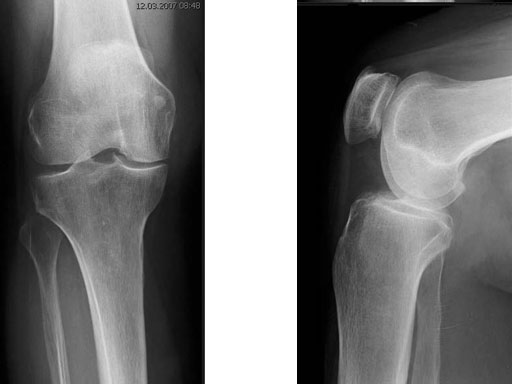

The correction is planned on a long-leg standing x-ray. After surgery, the mechanical axis should pass through a point 63% on the lateral side of the total width of the tibial plateau in the frontal plane. A transverse or slightly oblique incision is used to avoid damage to the saphenous nerve. The distal fibers of the medial collateral ligament are detached from the tibia. Under fluoroscopic control, two wires are placed in the proximal tibia marking the transverse osteotomy plane. The cut usually starts at the upper margin of the pes anserinus and ends at the tip of the fibula on the lateral side. The wires are placed exactly parallel to the tibial plateau thus taking into consideration the individual tibial slope of the patient. An incomplete cut of the posterior two-thirds of the proximal tibia is performed with an oscillating saw guided by the wires. Continuous irrigation avoids burn injury to the bone. A second osteotomy is now performed in the anterior third of the tibia in an angle of 100 ending above the patellar tendon insertion. A smaller saw blade is used and the complete anterior cortex is cut exactly in the frontal plane. The osteotomy is now gradually opened by inserting flat chisels or a spreader-chisel into the posterior osteotomy cleft. This process may take some minutes and can usually be completed without fracture of the lateral cortex. A bone spreader is now placed in the posteromedial edge of the tibia and the chisels are removed. The leg is extended and the correction is checked with the fluoroscope. A long metal rod is placed between center of the hip joint and center of the ankle joint. The projection of this rod should be at the planned point of correction on the tibial plateau lateral of the midline. Eccentric collapse of the medial joint space may cause accidental overcorrection. In this case pressure on the foot may simulate loading and body weight. The correction can be fine-tuned by opening or closing the spreader. The TomoFix Medial Tibia Plate is now placed in a subcutaneous pocket. The implant is precontoured and usually fits well to the bone surface. The distance holders avoid compression of the medial collateral ligament and the pes anserinus. Three proximal bolts are placed near the subchondral sclerosis zone. The position of the bolts is adapted to the anatomy of the proximal tibia giving optimum purchase for the bolts. An oblique lag screw is inserted distal to the osteotomy. This screw in the first combination hole allows careful compression of the lateral osteotomy hinge and pretensioning of the implant. A stab incision is created on the shaft and the implant is fixed monocortically with bolts. The lag screw and the distance holders are replaced by bolts. The medial collateral ligament is released longitudinally to reduce medial compartment pressure and the wound is closed in layers. An overflow drain may be used. Clinical and experimental work has proven that when this technique is closely followed, corrections up to and over 15 mm can be performed without bone grafting or use of bone substitutes.

A 68-year-old female.

Case provided by Alex Staubli, Luzern, CH